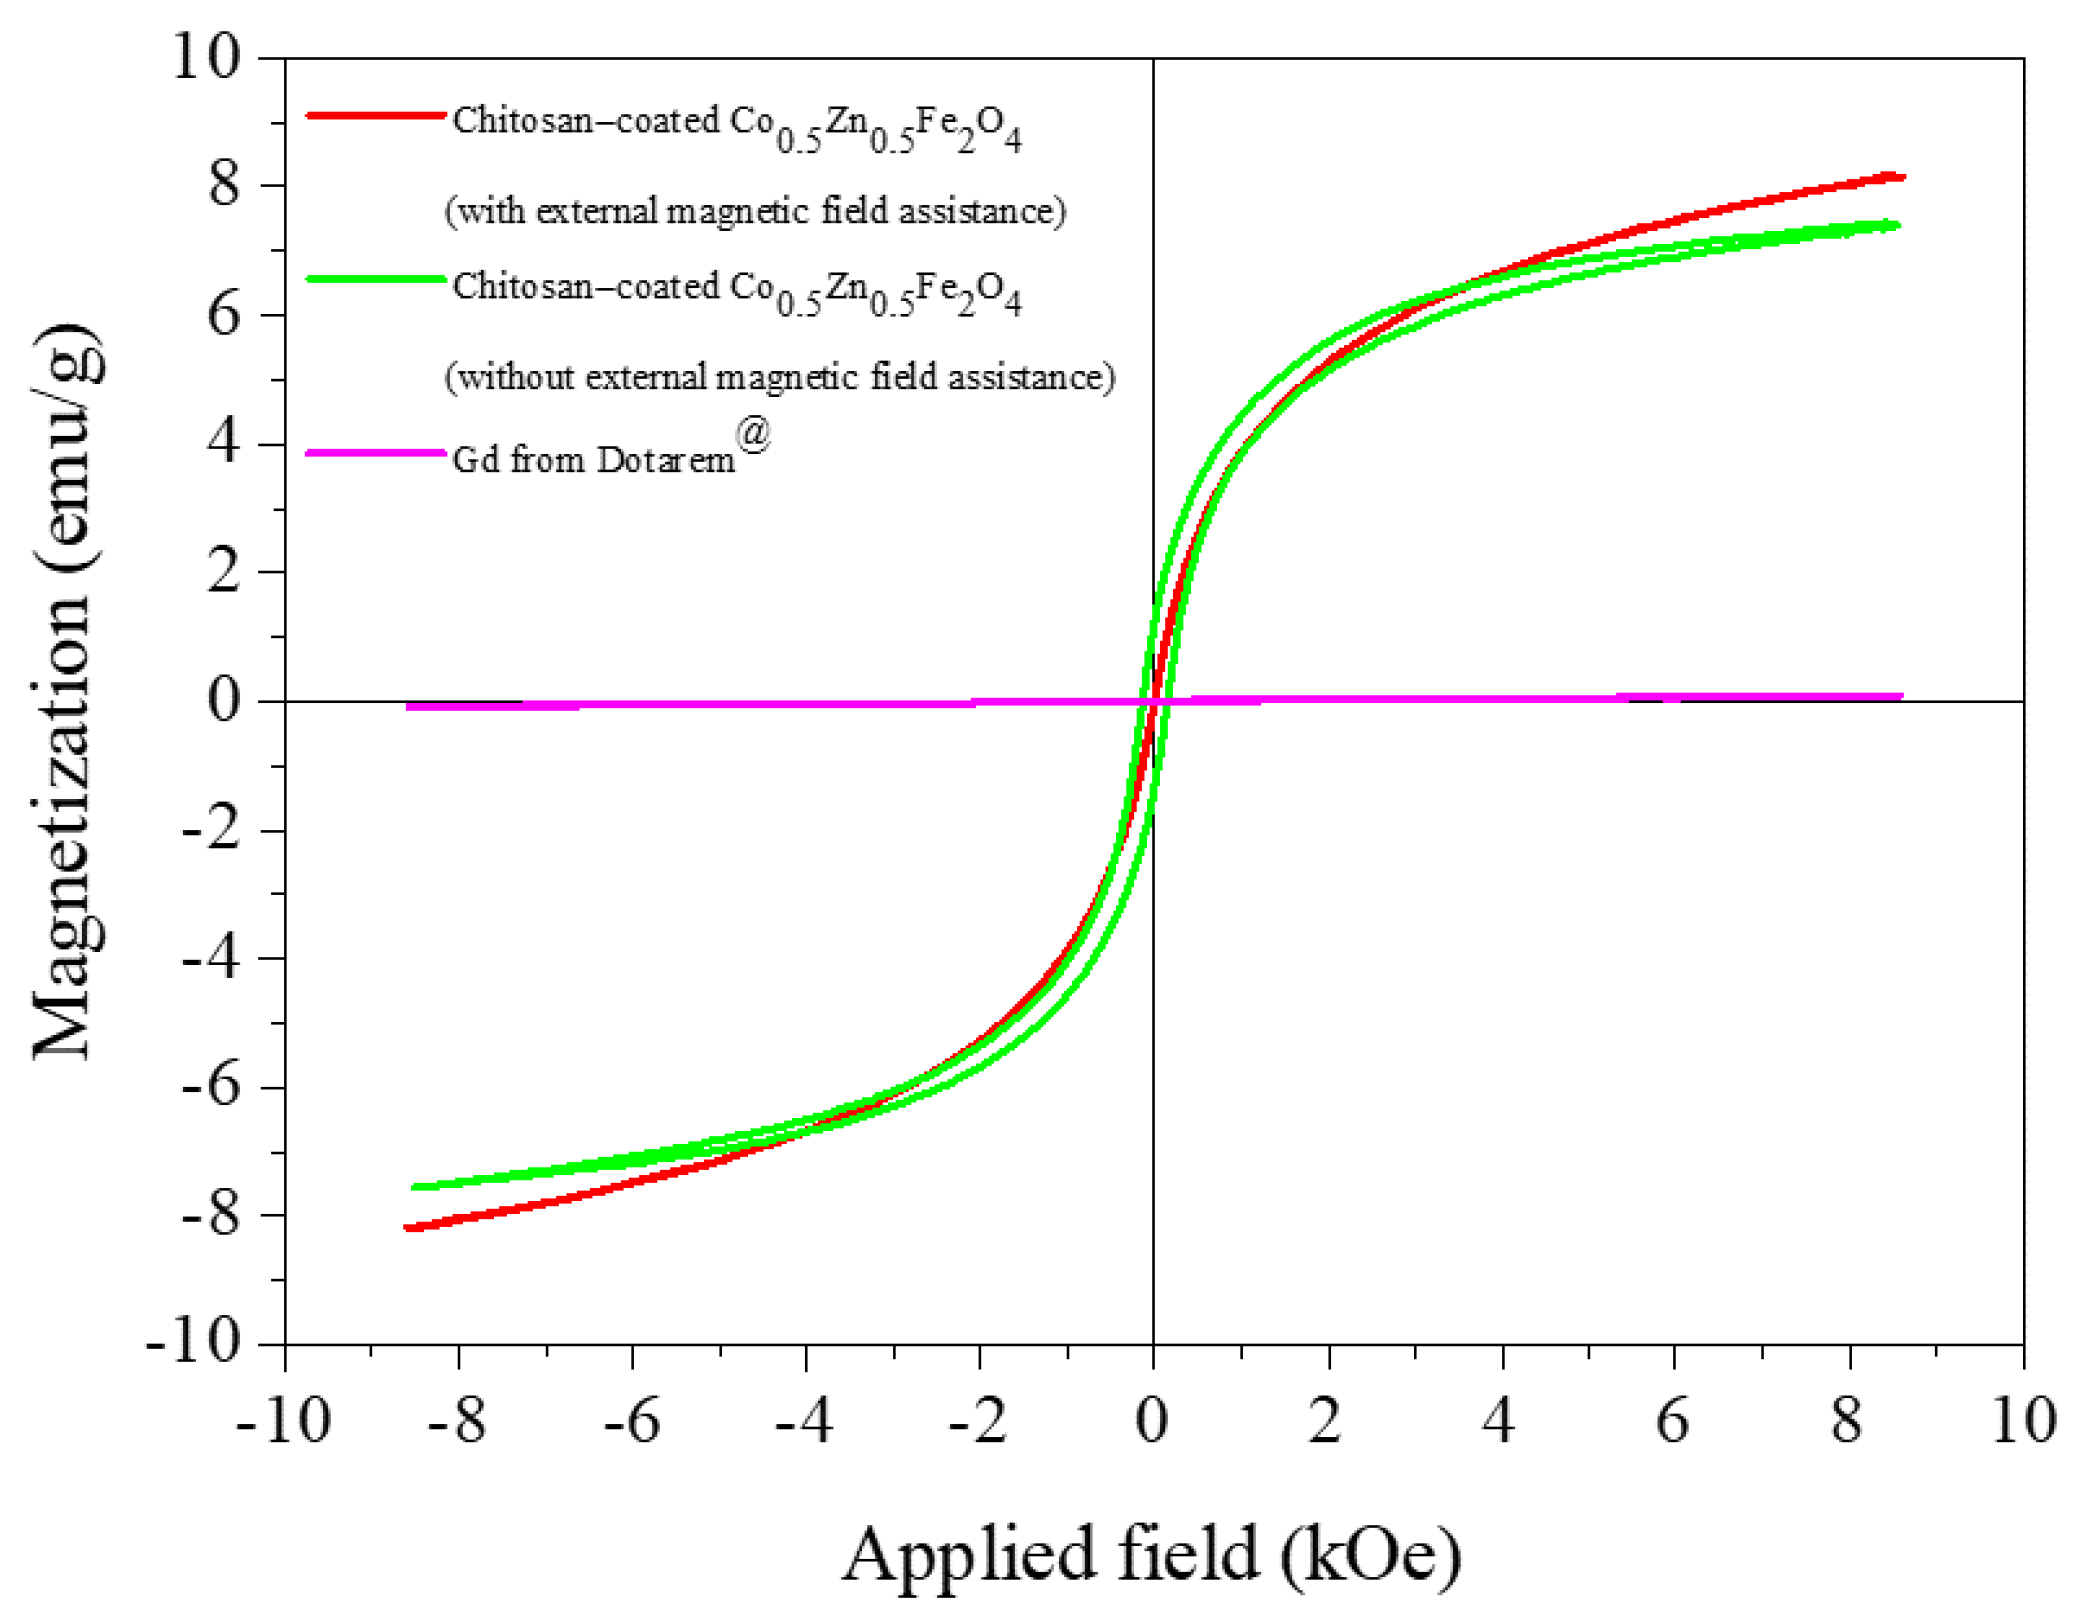

3.1. Material Characterization